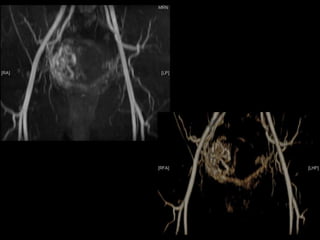

Dr. Hedvig Hricak

HISTORY

•   42 yo female

•   Recent immigrant from China

•   C/O postcoital and intermenstrual bleeding

•   Abnormal GYN exam

•   Abnormal biopsy

•   Further imaging performed

• What is the diagnosis?

• Staging?